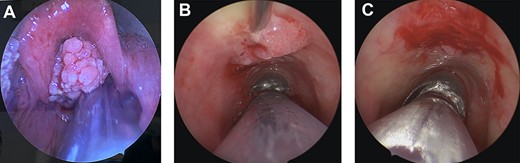

We planned to perform endoscopic sinus surgery with biopsy and excision of sinonasal tumour; however, on induction he was found to have a large supraglottic papillomatous lesion causing airway obstruction (Fig. 1A). Endoscopic assessment identified the extent of the sinonasal tumour, which involved the left anterolateral nasal wall, left septum (from Kiesselbach’s plexus to the posterior nasal septum) and then extended to the contralateral side through a perforation in the right mid septum and progressing to the anterior aspect of the right lateral nasal wall. The planned procedure was converted to a microlaryngoscopy with excision of supraglottic lesion, incisional biopsy of nasal papillomata and ligation of the left sphenopalatine artery (due to persistent bleeding). Tracheoscopy also identified a region of tracheal papilloma, which planned for surgical management later. Patient was extubated successfully and transferred to the High Dependency Unit for airway monitoring.

Intraoperative images. (A) Large, supraglottic, papillomatous lesion extending to petiole—excised at first surgery. (B) Tracheal papilloma being injected with Cidofovir at the base of lesion during second procedure. (C) Tracheal papilloma post debridement and injection of Cidofovir during the second procedure.

Histopathology confirmed inverted sinonasal papilloma in the left nasal cavity and right septum and exophytic sinonasal papilloma in the left lateral nasal wall. The supraglottic lesion was described as squamous papilloma—this confirmed our suspicion of concurrent sinonasal and respiratory papillomas, a rare combination of pathologies.

Two weeks later, he underwent a repeat microlaryngoscopy, tracheoscopy and debridement of tracheal papillomata with adjuvant cidofovir injection. The lesions treated were on the tracheal mucosa overlying the inferior aspect of the anterior cricoid and the left laryngeal ventricle (Fig. 1B and C). Four weeks later, an endoscopic septectomy, bilateral medial maxillectomy, right sphenoethmoidectomy and right sphenopalatine artery ligation were performed to eradicate sinonasal disease.